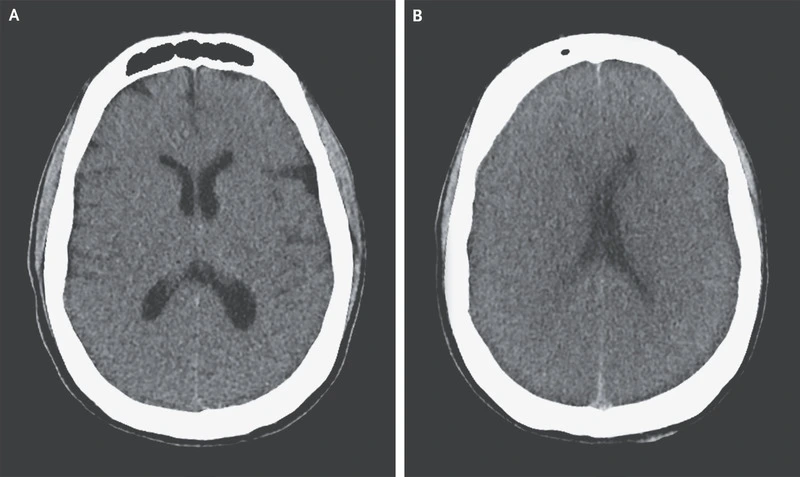

뇌사 환자의 뇌CT. 안타깝지만 뇌사환자의 의식이 돌아올 가능성은 없다. DM Greer, Determination of Brain Death, NEJM, 2021.

'이건 ㅇㅇㅇ님이 응급실에 도착했을 때의 뇌 CT입니다. 여기 뇌출혈이 보이시지요. 이 때는 보시다시피 출혈량이 많지 않았지만, 출혈 부위가 비특이적인 양상을 보입니다. 거기다 와파린도 복용 중이시고, 신장이식 받으신 것도 있기에 악화될 가능성이 굉장히 높았습니다.'

'이건 수술 직전 의식이 없어졌을 때 찍은 CT 입니다. 보시다시피 출혈량이 많이 늘어서 뇌가 심하게 눌려있습니다. 피가 많이나서, 원래는 두개골절제술을 해야해요. 두개골 안에 낑겨있는 뇌를 풀어줘야하거든요. 두피를 들어내서, 두개골을 손바닥만큼 잘라내고, 안에 있는 피도 제거한 뒤 두피만 봉합하는 수술입니다. 하지만 와파린을 드시고 계셔서 지혈이 안 되기에 수술하면 오히려 더 나빠집니다. 수술은 좋아지자고 하는거지 나빠지자고 하는게 아니잖아요. 그래서 두개골절제술 대신 안전하게 카테터를 꽂아야한다고 설명 드린것이고요'

'이게 방금 찍은 수술 후의 CT 입니다. 두개골 안에 관이 들어가있고, 고여있던 피의 양이 많이 줄었습니다. 설명드린대로 수술은 잘 되었고요. 하지만 뇌가 아직 많이 부어있습니다. 이런 말씀 드리는 저도 마음이 무겁지만, 결국 뇌사로 진행되는 것은 막을 수 없어보입니다'